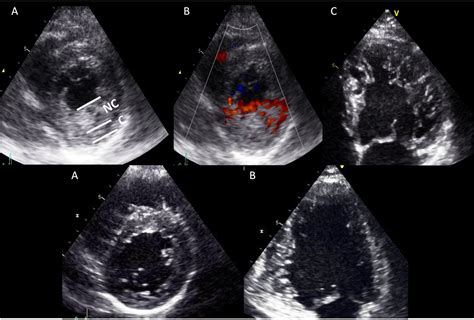

To better understand Non Compaction Cardiomyopathy, it is helpful to visualize the heart's anatomy. Typically, the heart walls are smooth and dense. In patients with NCCM, the myocardium (the heart muscle) remains thin and features excessive trabeculations—small, finger-like projections—and deep inter-trabecular recesses. These structural flaws create a "spongy" appearance when viewed through imaging techniques.

Diagnosing Non Compaction Cardiomyopathy primarily involves advanced cardiac imaging. Physicians utilize specific diagnostic criteria to differentiate NCCM from a normal heart that may just have prominent, yet healthy, trabeculations.

Echocardiogram The first-line imaging test to visualize structure and blood flow.